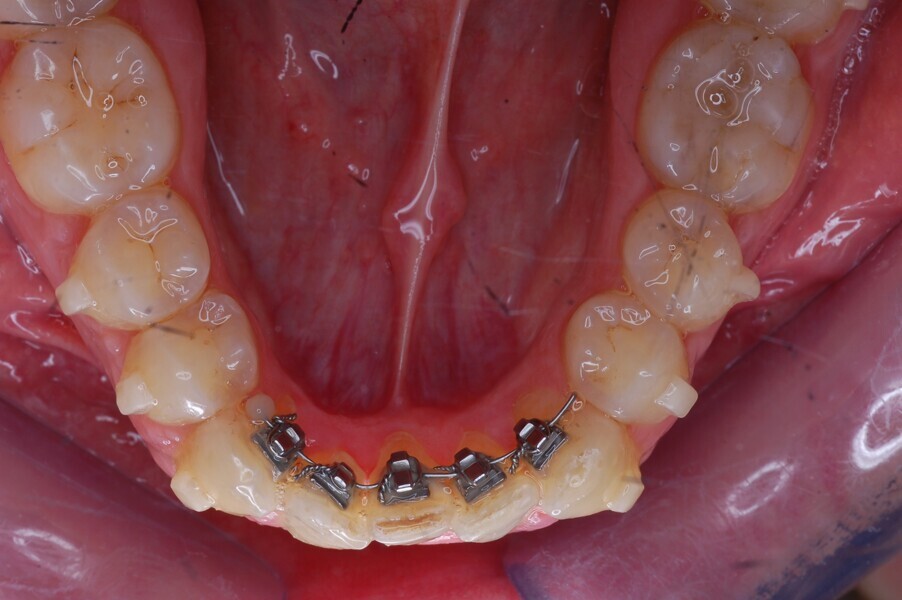

Fig. 45–50: Sequential frontal intra-oral photographs illustrating progressive levelling and alignment and uprighting of the mandibular right lateral incisor.

Fig. 46.

Fig. 47.

Fig. 48.

Fig. 49.

Fig. 50.

After 26 months, the HAT auxiliary was removed, and few refinement aligners for the final mandibular alignment were delivered to the patient. After a total treatment time of 28 months, composite restorations were performed on the maxillary incisors, and the patient received two rigid retention aligners for night-time wear.

The HAT technique requires the aligners to be adapted to the auxiliaries to create the necessary anchorage and allow tooth movement. The subsequent aligners were made to adapt to the lingual auxiliary to create the necessary anchorage so that only those teeth could be moved that required movement. This was done by creating 3D models used for thermoforming the aligners that resulted in the aligners having movement channels (spaces) incorporated into their design to allow teeth to move even when the aligners were placed over them. Teeth that were used as anchorage (the mandibular molars, premolars and canines) had no spaces so that the aligners fitted snuggly over them (Figs. 32 & 33). Rapid alignment was obtained in the mandibular anterior region in only nine weeks (Figs. 34–36). A prebent sectional 0.0175 × 0.0175 in. Gummetal wire was sent to us for the final stages of the alignment (Figs. 37–50).